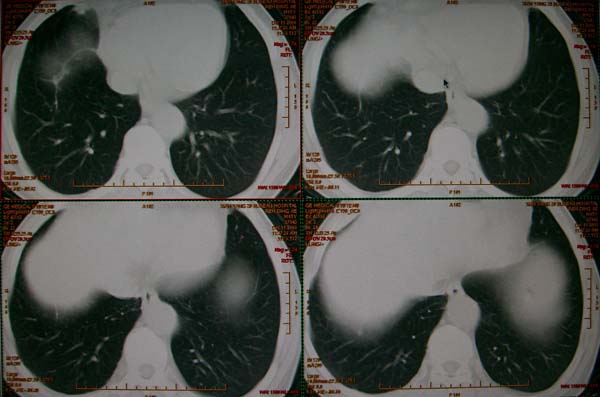

标题: CT17173:M65Y,咳嗽一月。请会诊 [打印本页]

标题: CT17173:M65Y,咳嗽一月。请会诊

右肺多发病灶,右上肺及下肺背段均有灶,考虑结核,

高度提示恶性病变(叶间裂及胸膜下可见结节),多原发或继发.建议高分辨及强化扫描.